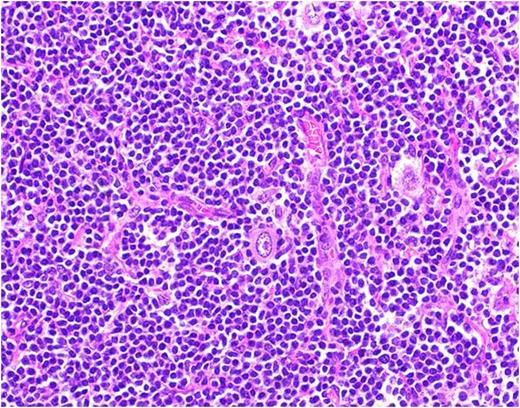

A 59 year old male with no significant medical history presented with progressive swelling and erythema of the right testis. Testicular cancer was suspected and he underwent a radical right inguinal orchiectomy. Pathology revealed a 5.7cm seminoma of the testis with lymphovascular invasion and without spermatic cord involvement (pT2) (Fig. 1). His tumor markers including AFP, LDH, and Beta-HCG were normal (S0). A CT scan of the chest, abdomen and pelvis followed by a PET/CT revealed enlarged, hypermetabolic mediastinal, hilar and periportal lymphadenopathy interpreted by the radiologist as concerning for metastatic disease. Given the atypical distribution for lymphadenopathy from testicular seminoma, an excisional biopsy of a left hilar node was performed and revealed Classical Hodgkin Lymphoma with IHC positive for CD15, CD30 and PAX-5 (Fig 2). He denied any B-symptoms and his bone marrow was uninvolved by lymphoma (stage IIIA). Adjuvant therapy for his germ cell tumor, otherwise an important consideration, was deferred and he began chemotherapy with adriamycin, bleomycin, vinblastine and dacarbazine (ABVD) for 6 cycles. Interim PET/CT after 2 cycles of ABVD showed a complete response. He has completed 6 cycles of ABVD and chose observation as opposed to single dose of adjuvant carboplatin for his seminoma and is currently under surveillance for both malignancies.